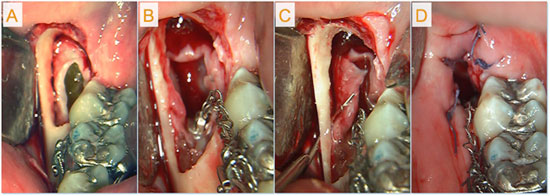

Subsequently, the cyst was marsupialized under local anesthesia, the crown of the impacted tooth was surgically exposed and an orthodontic buttonhole was bonded directly to it (Fig. 3). During surgery, an incisional biopsy specimen was taken from the cyst wall; histologic examination confirmed the initial diagnosis of dentigerous cyst (Fig. 4).

Figure 3: Surgery included: a) exposure of the cyst lumen; b) exposure of the crown of the third molar and bonding of an orthodontic buttonhole to it; c) creation of cortical perforations for marsupialization; d) partial wound closure.